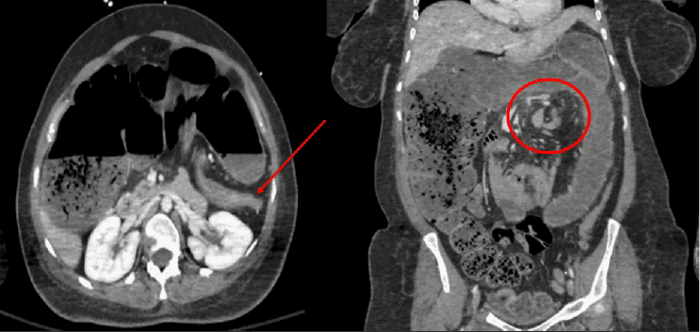

Upon initial physical examination in the ED, her blood pressure was 130/89 mmHg, pulse rate was 94 beats/minute, and temperature was 36.9°C. The abdominal examination was notable for a rotund, markedly distended, tympanic, and firm abdomen. Laboratory investigations revealed a normal hemoglobin and platelet count, with a white blood cell (WBC) count of 7.2 × 10⁹/L (reference range: 3.4-9.6 × 10⁹/L). Significant hypokalemia was present, with a serum potassium level of 2.7 mmol/L (reference range: 3.6-5.2 mmol/L). Her serum lactate was 1.3 mmol/L (reference range: 0.5-2.2 mmol/L), while her ammonia level was elevated at 73 mcmol/L (reference range: <51 mcmol/L), and arterial pH was 7.42 (reference range: 7.32-7.43). An episode of hypoxemia, with oxygen saturation dropping to 88% on room air, necessitated the initiation of supplemental oxygen at 2 liters/minute via nasal cannula. An immediate chest X-ray revealed significant colonic distension (Figure 1). Subsequently, an abdominal computed tomography (CT) scan was obtained, which demonstrated a large bowel volvulus localized to the region of the splenic flexure, with marked distension of the proximal large bowel up to 11 cm in diameter (Figure 2). A urinalysis was positive for a urinary tract infection, and intravenous ceftriaxone was initiated.

Figure 1. Initial Chest Radiograph Demonstrating Colonic Distension. Published with Permission